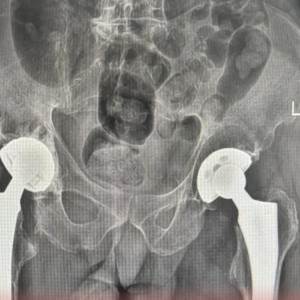

В Коврове медики освоили передовые методы лечения переломов тазобедренного сустава

Они успешно провели операции по эндопротезированию.